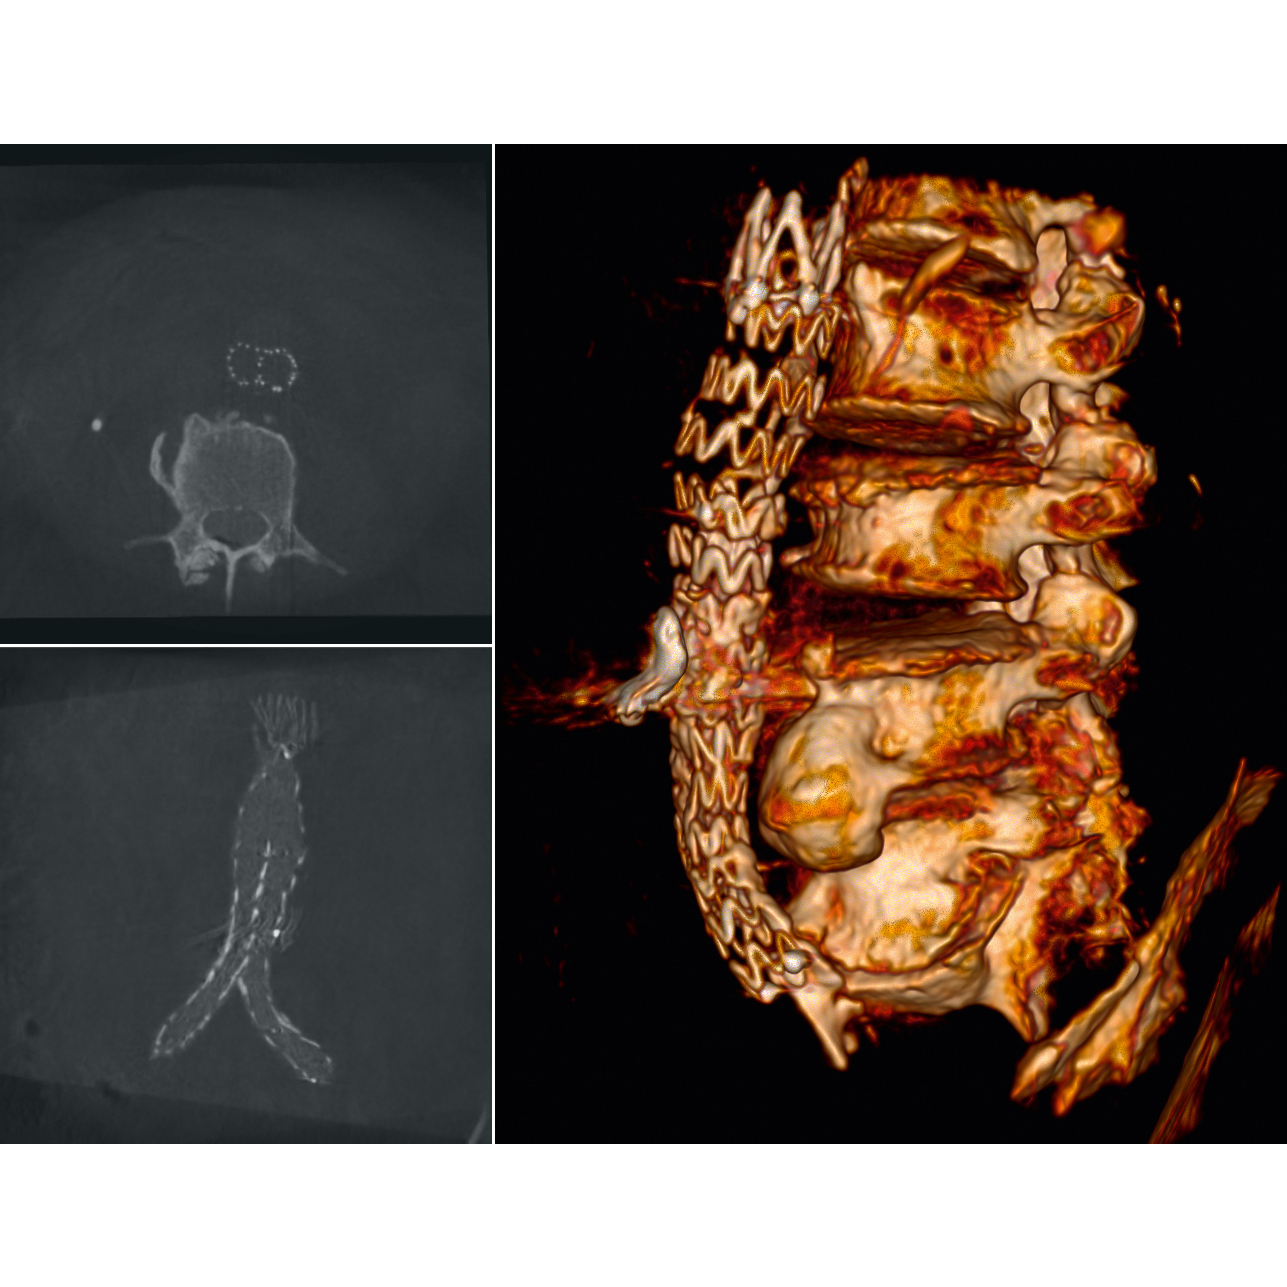

The Ziehm Vision RFD Hybrid Edition offers SmartVascular workflows tailored specifically to hybrid interventions for a seamless transition between fluoroscopy, digital subtraction angiography (DSA), and roadmapping (RSA). The open injector interface is supplemented by a CO₂ option, allowing patients with contrast agent intolerance to also be treated successfully.